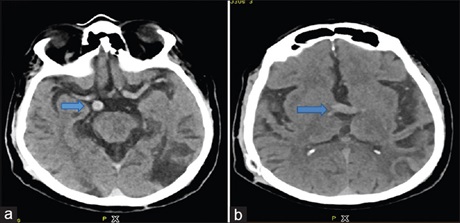

Vertebrobasilar Dolichoectasia

Dr. Eswaradass Prasanna Venkatesan, Ramasamy Balakrishnan, Kalidoss Ramadoss, G. Gnanashanmugham (Author)

93-95